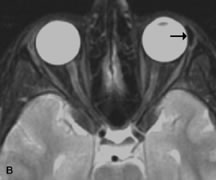

Tl relaxation time is the time required for the energized nuclei to give up the excess energy that was acquired from the RF pulse (high-energy state) and re-establish equilibrium (low-energy state) with the main magnetic field. The excess energy is released by these excited nuclei to the surrounding molecular environment, or lattice, and results in T1 relaxation, also called spin-lattice relaxation time. In different biologic tissues, hydrogen has a Tl ranging from a few hundred milliseconds to a couple of seconds. This range exists because local tissue factors affect the ability of specific protons to give up energy to the surrounding tissues. For example, hydrogen atoms attached to the carbon atoms of fat molecules relax much more rapidly than those attached to the oxygen atoms of water molecules. Viscosity, concentration, temperature, and molecular environment of the hydrogen atoms in the tissues also affect the T1 relaxation time. On a T1-weighted orbital image, fat, which has a very short T1 relaxation time, yields a high-intensity signal; the rectus muscles, which have an intermediate T1, yield an intermediate-intensity signal; and the vitreous, which has a long T1, yields a low-intensity signal (Fig. 8).5,8,16